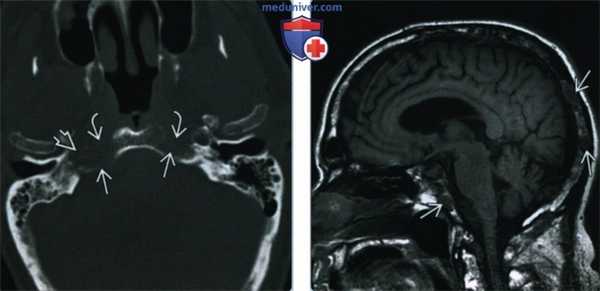

(Слева) При аксиальной КТ в костном окне определяются почти симметричные двусторонние литические очаги затылочной кости при множественной миеломе. Из-за симметрии эти изменения могут быть менее заметны, но отмечается исчезновение наружного кортикального слоя, в норме отображающеюся в виде белой линии. Обратите внимание на эрозию кости правого канала сонной артерии.

(Справа) При МРТ Т1 в сагиттальной проекции определяются множественные низкоинтенсивные очаги множественной миеломы. Этот режим (без FS) относительно чувствителен к злокачественным процессам кости, особенно при контрастировании всею черепа и/или при записи постконтрастных снимков.

(Слева) При МРТ Т1FS c КУ в аксиальной проекции у пациента с парезом правого лицевого нерва определяется равномерно контрастируемая опухоль, состоящая из костного и внекостного компонентов, вызывающая деструкцию сосцевидного отростка правой височной кости и облитерирующая шилососцевидное отверстие. МРТ T1 FS с КУ, как правило, является наиболее чувствительной методикой диагностики поражения костного мозга.

(Справа) При корональной МРТ Т1FS с КУ определяется контрастное основное объемное образование ската затылочной кости и более мелкие миеломатозные новообразования свода черепа и правой нижневисочной ямки.